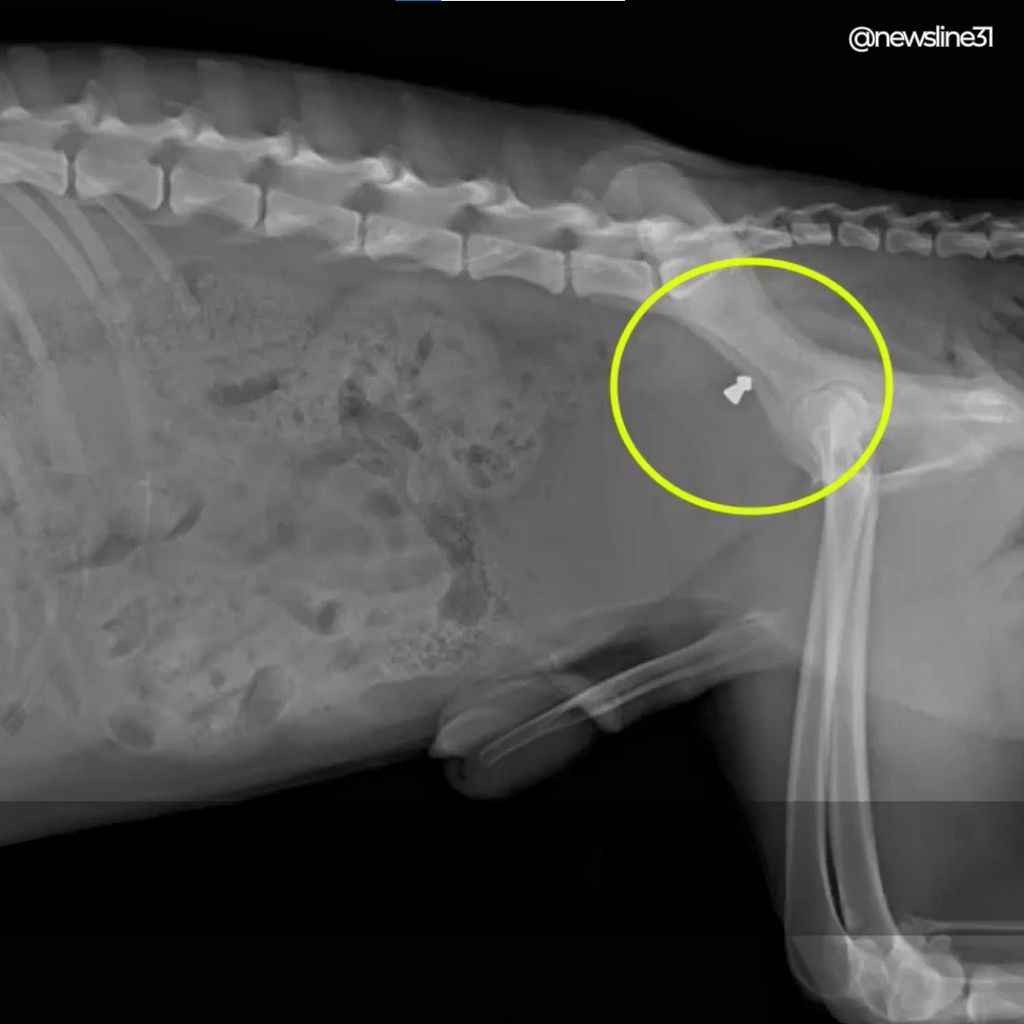

We believed Atay’s limp was from an old accident. Something tragic, but ordinary. Then the X-ray appeared on the screen. There was a bullet inside his body.

In that instant, everything made sense. The fear. The constant alertness. The way he watched hands instead of faces. Someone had intentionally hurt him. Someone had chosen cruelty toward a dog who had done nothing wrong.

We cried. Not only for the pain he endured, but for the trust he had lost. The veterinarian explained that surgery wasn’t possible. Too much time had passed. Instead, Atay would need long-term care, gentle exercises, and consistency. Healing would not come from medicine alone.